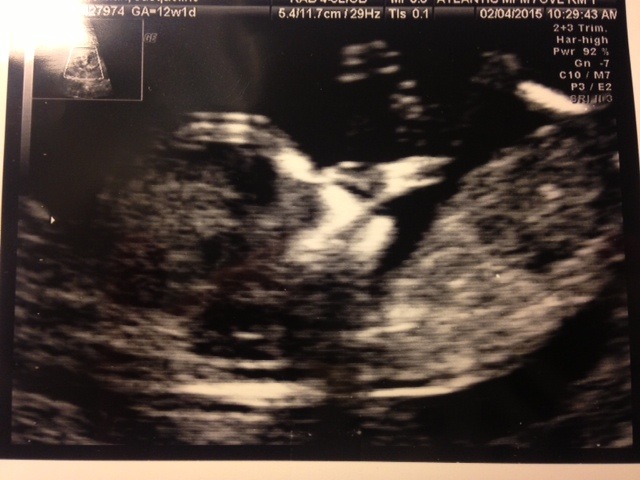

Hello! I am attaching my 12 week ultrasound. Any guesses? Thanks!!!

Also- Is that a nub or a leg joint?

Thanks! How about the skull?